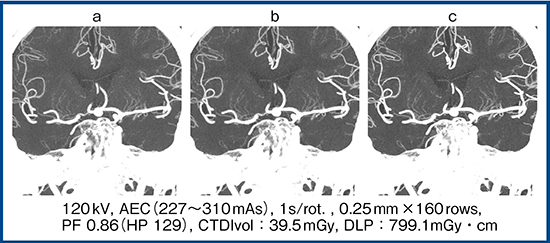

Aquilion Precisionでは,Full IRの逐次近似画像再構成技術“FIRST”が,2017年秋から使用可能となった。図1は,Aquilion PrecisionでのMCAの穿通枝領域をFBP(a),AIDR 3D(b),FIRST(c)で再構成した画像だが,FIRSTではより末梢まで明瞭に描出されており,今後,超高精細CTにおいてもFIRST適用による高画質と低被ばく化が期待される。

図1 画像再構成法による脳底動静脈の描出能の比較

a:FBP b:AIDR 3D c:FIRST